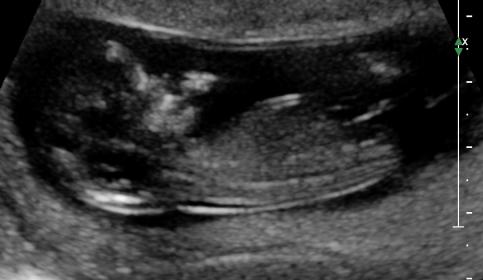

Hello, Please guess my scan pic. I really appreciate it. This is our second and happy with any gender.

Any guesses? measuring 12 w 2 days